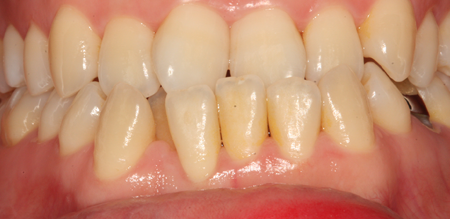

치주염 단계별 증상

건강한 상태

치아 주위의 잇몸이 핑크색을 띄며, 잇몸에서 피가 나지 않음.

스케일링을 6개월 ~ 1년 주기로 받고 올바른 칫솔질로 건강한 치주 조직을 유지

치은염 (초기~중기)

치아 주위의 잇몸이 붉게 부어 있으며, 칫솔질 등을 할 때 피가 남.

스케일링 주기의 조절이 필요할 수 있으며, 올바른 칫솔질을 시행하여야 함.

치주치료 전후사진

B

A